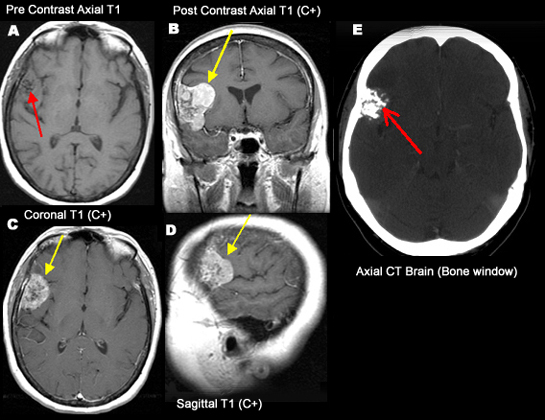

Partially Calcified Meninigioma

• A-D: MRI

• A: Arrow points to punctate low signal on the right side corresponding to calcifications in CT.

• BCD: Enhancing mass with low signal consistent with partially calcified meningioma involving right fronto-lateral dura.

• E: CT shows focal calcifications in the site of mass.

66 year-old lady presented with numbness involving the left upper and lower extremities.

An enhancing (arrows) and partially calcified meningioma (red arrows in A and E) involving the right anterior-lateral frontal dura.